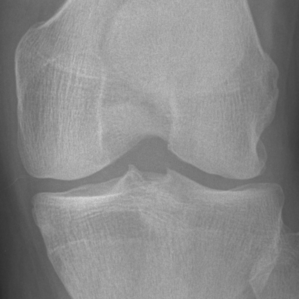

Since the aim of this study is the early detection of knee OA (KL=0 vs. KL=2), we focused on the characteristics of the lateral and medial sides of the knee joint. We used the same ROIs as [chen] available at put a reference for the link. ROIs were extracted from the original X-ray images using YOLOv2 [yolov2]. Then, the fully automatic segmentation method proposed in [tiuplin] to extract the patches was used. Firstly, two 128×\times×128 pixel square patches were cropped from the left and right parts of the knee joint to cover the whole distal area. Secondly, the patch from the medial side was flipped horizontally. Finally, the two patches were used as inputs of the learning model.

Refer to caption

Figure 3: (a) Original knee radiographs from OAI, extracted ROI in red. (b) Obtained patches in blue and orange boxes. (c) Extracted patches for the two sub-networks respectively